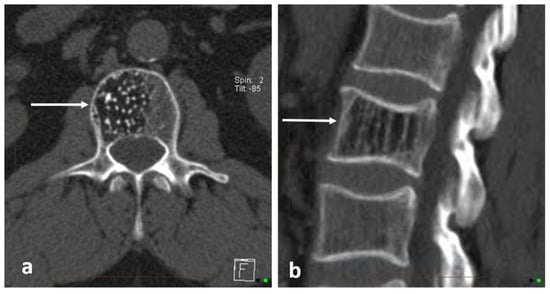

3.3. Osteoblastoma

| Osteoblastoma | Expansile lucent lesion. Sclerotic rim. Bone destruction. Variable intralesional ossification. | Low to intermediate T1 signal and intermediate to high T2 signal. Surrounding soft tissue oedema, extra osseous soft tissue component. |